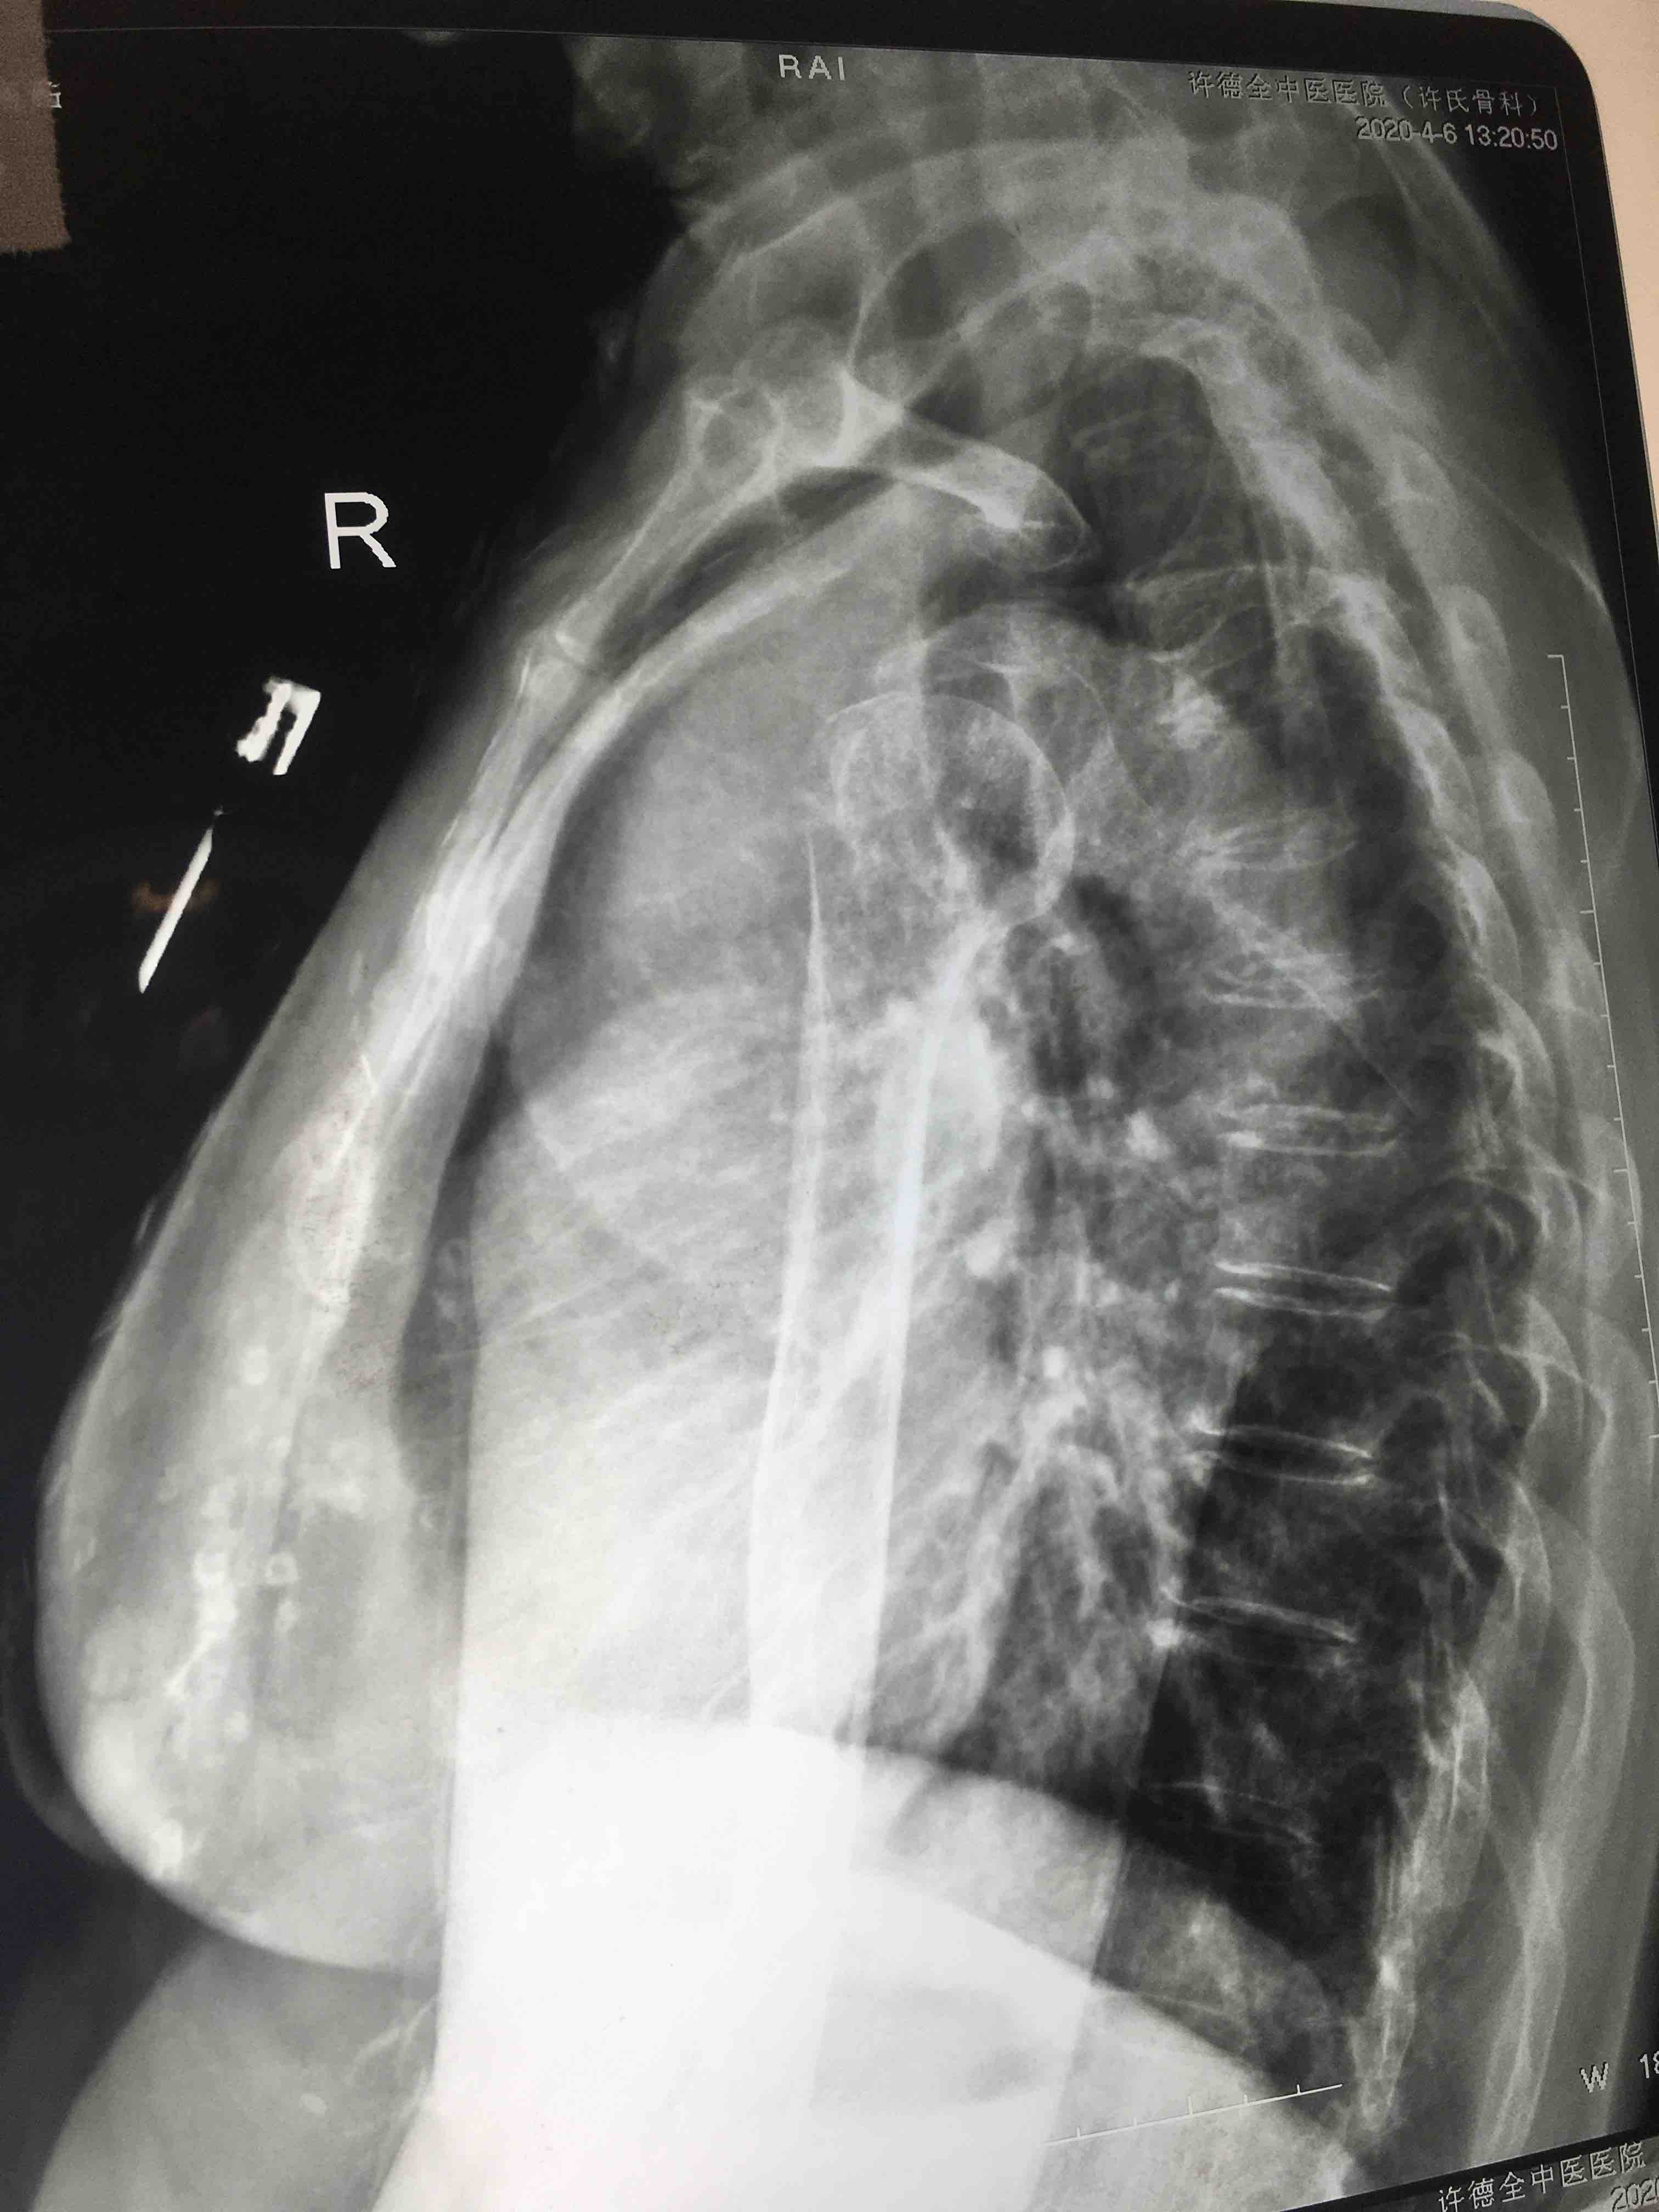

骨折 肱骨外科颈骨折

摔伤后右肩部肿痛,活动受限1小时入院。既往身体一般,无特殊不良嗜好。

生命体征平稳,心肺复未见异常。右肩部肿胀明显,局部皮色发红,皮温高,压痛及纵向叩击痛阳性,肩关节活动受限,末梢血运感觉正常。

诊断右肱骨外科颈粉碎性骨折在臂丛麻醉下行切复内固定术,术后抗炎,消肿等处理。